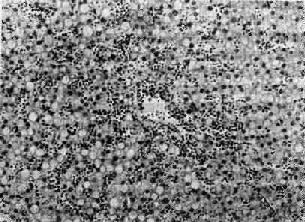

长期淤血,由于氧和营养物质供应不足和代谢中间产物堆积,还可引起实质细胞的萎缩和变性。如慢性肝淤血时(图3-2),肝细胞萎缩(主要在肝小叶中央带)和脂肪变(主要在小叶周边带),以致肝切面呈现槟榔状花纹,称为槟榔肝(nutmeg liver)。较急性且程度严重的肝淤血可引起肝细胞坏死。

图3-2 慢性肝淤血

肝窦扩张充血,肝细胞脂肪变性